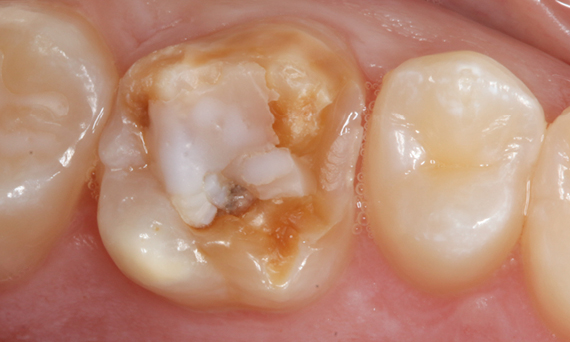

Before: Large insufficiency of the composite filling on tooth 16 with distal marginal ridge cracks, a lingual wall crack and distal recurrent decay.

After: Highly aesthetic full-surface glass-ceramic crown.